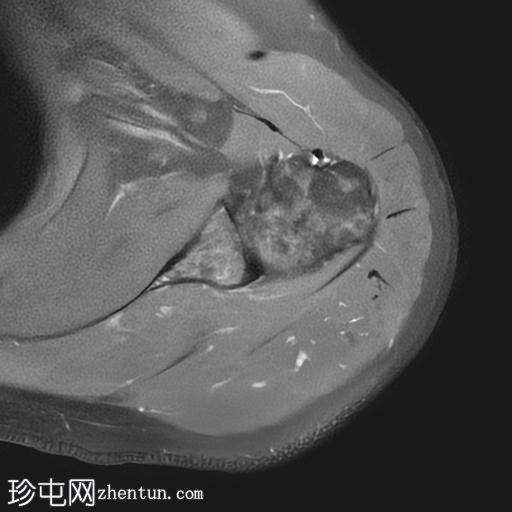

轴位PD序列

冈上肌腱中后部关键区及肌腱止点纤维可见一低信号椭圆形病灶,大小约5 x 8 x 16 mm,提示钙化性肌腱炎。

肩锁关节轻度关节囊肥厚及退行性改变。

肩峰类型:II型

肩袖钙化性肌腱炎是一种自限性疾病,由羟基磷灰石钙沉积引起,最常见于冈上肌腱。